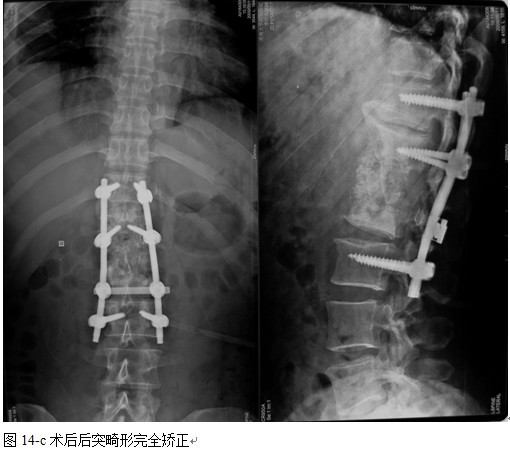

本组手术用时间3~4h , 平均3.5h 。术中出血300~500ml , 平均约350ml 。术后症状完全缓解,无神经功能障碍加重等并发症,1例营养差的老年患者伤口出现窦道,1例因肝功能差,术后未口服抗痨药,伤口出现窦道,经换药后二期愈合,其余病例伤口均一期愈合。马尾神经受损的患者术后基本恢复正常。术后一周后凸角平均 5.4°后凸畸形平均矫正90%以上, 最终后凸角平均8.3°,后凸角度平均丢失4.2°。随访3个月有87%(40/46)有骨痂形成,6个月91.3%(42/46)明显骨性愈合(见图),其余4例9-12个月内愈合,随访时间3-32个月,平均11个月,46例患者中2例在术后2个月和3个月时背部形成脓肿,换药后治愈。2例出院1月后并发结核性脑膜炎,治疗后好转。1例因椎弓根钉偏外,刺激神经根,5个月后从侧方脱出,疼痛加重,因前后路植骨完全愈合,取出后症状完全缓解。

中国学者金大地[22]等采用一期前路病灶清除植骨前路钢板固定治疗腰椎结核,平均18°的后凸畸形得以矫正,Mukhtar[23] AM等采用前路病灶清除植骨分期或同期后路固定治疗腰椎结核22例,术后后凸畸形矫正度数平均为27°。从我们的随访结果看,术后后凸畸形平均矫正度数为26.9°,后凸畸形平均矫正90%以上, 6个月-49个月后随访,后凸角度平均丢失4.2°。本术式也适用于结核所引起的弹性差的后凸畸形,对于病灶纤维化或骨化的非弹性后凸畸形,后路固定后,先行前路病灶、纤维化或骨化切除、松解,逐步刮除病灶、逐步撑开,达到畸形矫正和植骨的目的。